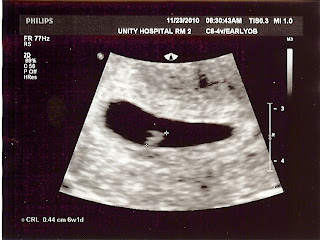

Yesterday was a good day! We had our official ultrasound at the clinic. The baby's heartbeat was up to 139 beats per minute, which is excellent! Baby measured at 7 weeks 2 days, which moves our OFFICIAL due date to July 17, 2011!

Amy has only gained 1 lb so far, which is good. The goal is not to gain more than 5 lbs in her first trimester. She's still been emotional (the Dr informed her that Progesterone shots will increase the "hormonalness" of being pregnant).